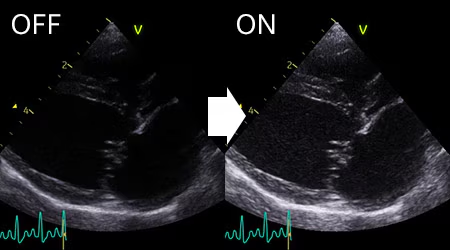

Auto Gain

従来はViewを変えるたびに必要だったゲインやTGCの調整が不要になり、ボタンひとつで距離、方位分解能の均一性と輝度をリアルタイムに最適化した画像を抽出で切るようになりました。